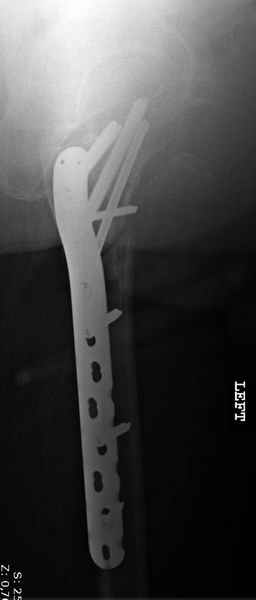

Применили проксимальную Synthes Locking plate, из-за множественных фрагментов посчитали более приемлемым в этом случае (клиника университетская, резиденты должны имет возможность созерцать разные варианты остеосинтеза).

Также старался минимизировать доступ на уровне перелома с субвастус доступом, диафиз фиксирован перкутанно, не стали гонятся за малым вертелом, как смог зафиксировал.

Перелом из четырех фрагментов, не стабильный (лекция Michael R. Baumgaertner, http://www.hwbf.org/ota/bfc/baumg/exp.htm), нужна стабильная фиксация.

Фиксация таких нестабильных чрезвертельных и reverse obliquity субтрохантерик переломов всегда была сложной задачей и ранее использовали Blade Plate. Но многие локальные общие ортопеды, к которым, в основном поступают такие больные, имели трудности с применением импланта, где необходимо было точная калькуляция по введению Blade и поэтому Synthes разработал Proximal Locking plate как альтернативу, где три проксимальные шурупа в разных направлениях создают концепцию угловой стабильности Blade Plate.

Со второго дня движения в суставе, контрольный осмотр через две недели и в зависимости от рентгенологического сращения, дозированную нагрузку с постепенным увеличением начнем через 5-6 недель.